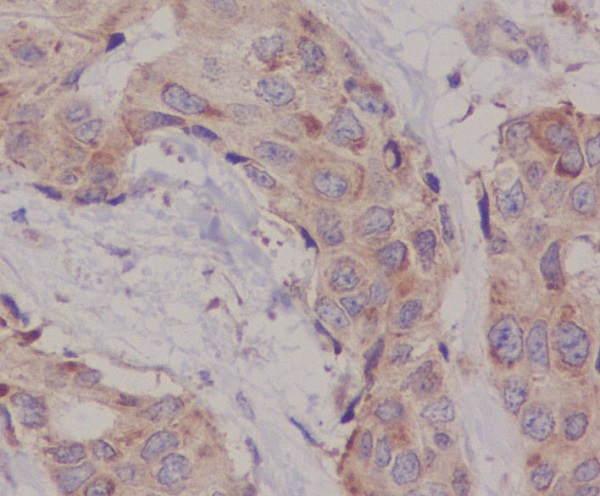

Immunohistochemical analysis of paraffin-embedded human breast cancer, using Hsc70 Antibody.